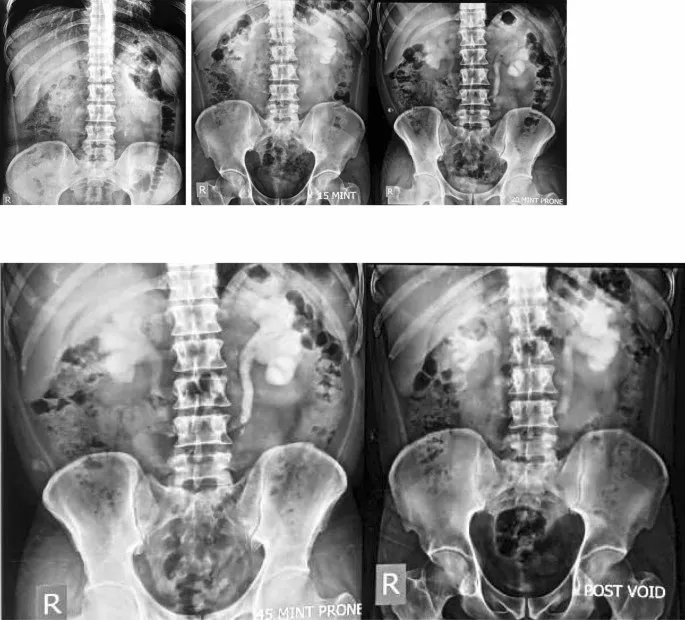

- The Dye's Journey (Standard IVU Protocol):

Serial abdominal radiographs track dye excretion.

- Phases & Timing:

- Nephrogram: 1 min (renal parenchyma).

- Pyelogram: 3-5 min (calyces), 5-15 min (PCS, ureters).

- Cystogram: 25-30 min (bladder).

- Uses iodinated contrast; key images include nephrogram, pyelogram, and post-void views.